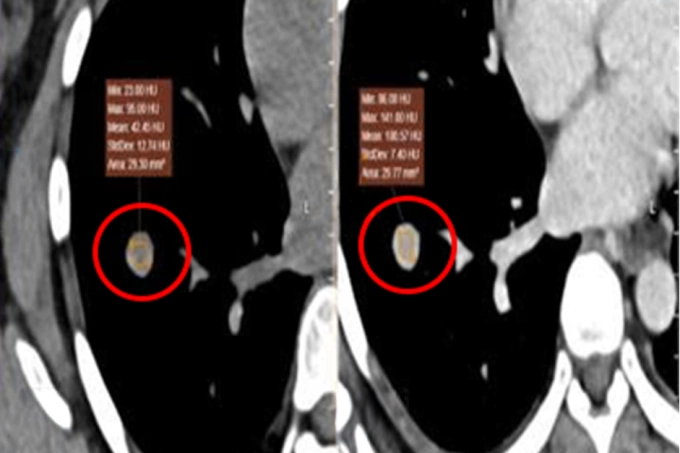

Ảnh CT cho thấy khối u ở thực quản (khoanh đỏ). Ảnh: Bệnh viện Đa khoa Tâm Anh